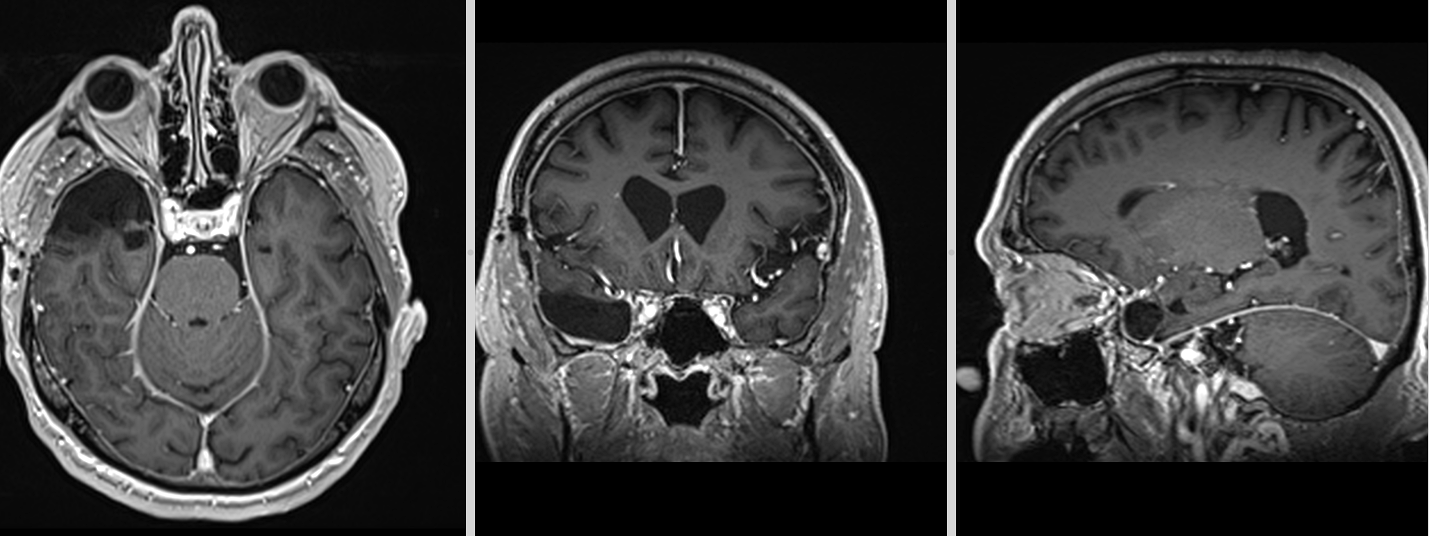

Vă prezentăm cazul unui pacient diagnosticat cu meningiom de aripă de sfenoid dreaptă, o tumoră cerebrală benignă care se dezvoltă din meningele ce acoperă creierul. Deși meningiomele sunt în general tumori cu evoluție lentă, localizarea lor în apropierea structurilor importante ale bazei craniului poate produce simptome neurologice și necesită frecvent tratament chirurgical.

Pacientul s-a prezentat pentru evaluare neurologică după apariția unor simptome persistente, care au determinat efectuarea unui RMN cerebral. Investigația imagistică a evidențiat o formațiune tumorală situată la nivelul aripii sfenoidului drept, cu aspect caracteristic de meningiom.

Având în vedere dimensiunea și poziția tumorii, s-a recomandat tratament chirurgical, obiectivul intervenției fiind rezecția completă a leziunii și decompresia structurilor cerebrale învecinate.

RMN postoperator precoce